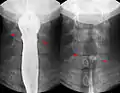

Abdominal X-ray showing small packages of cocaine swallowed by a trafficker.

Fishbone pierced in the upper esophagus.Left image during swallowing contrast medium, right image after swallow only dimly visible.